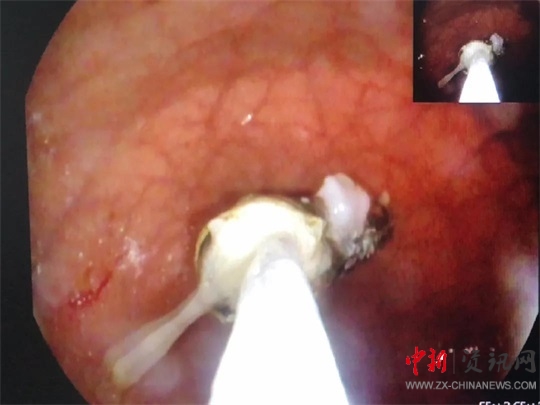

全身麻醉后,醫(yī)生龔靈輝操作胃鏡進入孩子胃部,發(fā)現(xiàn)一節(jié)電池浸在胃液里。由于患兒年齡小,胃部體積也很小,長達5cm的電池顯得特別巨大,同時胃鏡下的操作空間也很有限,為手術(shù)帶來了不小的麻煩。

在手術(shù)過程中,患兒多次血氧飽和度直下,醫(yī)生不得已拔出胃鏡,進行搶救,情況十分危險。因電池較長,在取的過程中,幾次卡在食管里。為了防止劃傷食管,龔靈輝不停地變換鏡子的角度,最終找到一個合適的角度下了圈套器,在護士宋惠澤和麻醉科醫(yī)生岳娟娟的配合下,歷經(jīng)十幾分鐘把電池像網(wǎng)魚一樣“網(wǎng)”了出來。孩子面色紅潤,生命體征平穩(wěn),手術(shù)順利結(jié)束,所有人都松了一口氣。